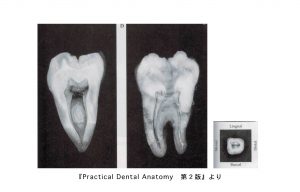

下顎第一大臼歯の中身

• 歯の外形を縮小した形。

• 髄室角は近心側ほど鋭く突出。近心舌側は近心頬側より鋭く、高く突出している。

• 根管数は2〜4根管

• 近心根は頬舌的に分岐した2根管性(80%)が多く、遠心根は1根管性(70%)が多く認められる

• 根尖孔付近は強く狭窄されて細く、小さく彎曲していることが多い。

下顎第二大臼歯の中身

• 髄室角の突出は第一大臼歯より弱い。

• 根管の数は2〜4根管で通常は3根管が多い。近心根は2根管性(70%)、遠心根は1根管性が多い。

• 頬側根管は細く彎曲するものから幅広いものまで認められる。

• 隣接面からみると、舌側根管は舌側に凸彎し、頬側根管は頬側に凸彎している。